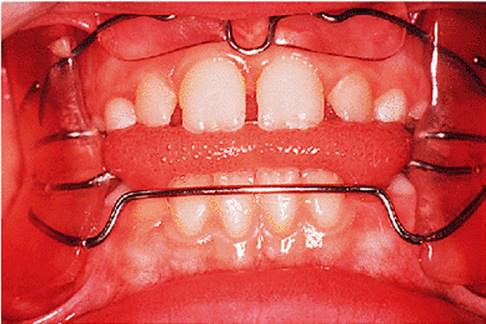

Before discussing functional appliances in detail, Fig. 18.1 gives an overview of this type of functional appliance in clinical use. This patient has a Class II division 1 malocclusion of the type for which functional appliances are very suitable, and for which they have been used for many years.

There are a number of important features to note which will be discussed further later in the chapter. First, the patient is still growing and the signs are that her pattern of facial growth is likely to be favourable. Although the skeletal pattern is Class II, the vertical relationships are close to average and the direction of mandibular growth is likely to be a mild forward rotation (see Chapter 4) which is favourable to the correction of a Class II malocclusion. Second, the soft tissue morphology is favourable despite the lips being incompetent, with the lower lip resting behind the upper incisors. The lower lip line is above the level of the upper incisal edges, and after the overjet has been reduced the lower lip will rest labially to the upper incisors, so helping to resist any tendency for relapse of the overjet. Third, the arches are well aligned — functional appliances have no mechanism for treating irregularities of alignment of the teeth.

The appliance holds the mandible in a forward postured position, in this case with the incisors edge to edge (Fig. 18.1(f)). The facial musculature is thus stretched, and applies a posterior force to the upper arch and an anterior force to the lower arch. The lower incisors have acrylic capping to prevent excessive labial tilting of the lower incisors, and this also serves as a bite-plane to reduce the overbite (Chapter 10). The appliance must be worn for at least 14–16 hours each day, but once the overjet has been reduced fully the amount of daily wear can gradually be reduced to sleeping hours only. The patient should continue to wear the appliance overnight in this way as a retainer, at least until the period of rapid pubertal growth is complete. Figures 18.1(g) and 18.1(h) show the dental and facial changes which occurred during treatment.

Fig. 18.1. (a) This 12-year-old girl had a skeletal II facial pattern and average facial proportions. The lips were incompetent with the lower lip lying below the upper incisors at rest. (b), (c) She had a Class II division 1 malocclusion with an overjet of 10 mm, the overbite was increased and complete, and the molar relationship was Class II on both sides. (d), (e) The upper and lower arches were well aligned. (f) A functional appliance (an activator) was fitted. (g) The corrected occlusion with Class I incisor and molar relationships. (h) The patient's facial profile at the end of treatment.